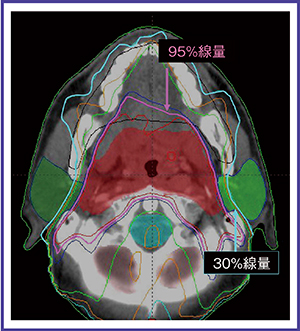

逆方向治療計画の実際

逆方向治療計画を行うに当たっては,まず患者を肩まで覆うシェルで固定し,CT撮影を行う。標的体積やリスク臓器の輪郭入力は,2mmスライスのCT画像上で行う。IMRTでは,この輪郭に沿った線量分布が作成されるため,IMRTが成功するか否かはこの輪郭入力によるところが大きい1)。肉眼的腫瘍体積(GTV)を設定するに当たって,頭頸部癌では,CT画像や触診所見に加えFDG-PETやMRIの画像を参照する必要がある。当院では,頭頸部癌に対しては原則として,PET/CTシミュレーションによる治療計画を行っている2)(図2)。PET/CTシミュレーションの利点は,GTVを決して外さないという自信を持ってCTVの輪郭入力ができることにある。さらに,CTVに対して治療中のシェル内での臓器の動きや,毎回の治療のセットアップエラーなどを考慮した3〜4mmのマージンを加えてPTVとする。

輪郭入力に引き続き,目標とする治療計画のPTVの最大線量(D0)および最低線量(D100),各リスク臓器の最大線量(D0),あるいはそれぞれの重要度(priority)などを設定し,逆方向治療計画を行う。脳や脊髄ではD0のみを規定するが,耳下腺などではD50(median dose),D25なども規定する。

図2 上咽頭癌のPET/CTシミュレーションによる線量分布

CTのみでは進展範囲の同定が困難であった頭蓋底浸潤の範囲が正確に把握できた。